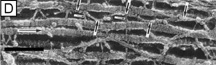

Although difficult to count exactly, the central cornea has been found to have approximately 300 corneal lamellae, whereas the peripheral cornea has approximately 500.61 Although these lamellae are generally described as running parallel to the corneal surface in orthogonal directions to one another, regional difference exist in their size, directionality, and amount of interweaving. The anterior third of the cellular corneal stroma has thinner (0.2- to 1.2-μm thick), narrower (0.5- to 30-μm wide), and mostly obliquely oriented lamellae with extensive vertical and horizontal interweaving (Figs. 12B and 13B), whereas the posterior two-thirds has thicker (1- to 2.5-μm thick), wider (100- to 200-μm wide), and mostly parallel oriented lamellae with only slight horizontal interweaving (Figs. 12C and 13C).60

Additionally, only lamellae in the posterior two-thirds of the cellular cornea stroma run in the classic orthogonal directions, whereas all of the lamellae of the anterior third and a minority of lamellae in the posterior two-thirds run in nonorthogonal directions. Because the lamellae in the anterior-most layers of cellular stroma branch so extensively, it is not surprising that they also interweave with (i.e., are attached to) the Bowman's layer in a polygonal fashion, creating a mosaic appearance that can be seen on the anterior corneal surface under certain circumstances (Fig. 12A, inset). Finally, all corneal lamellae appear to stretch across the cornea from limbus to limbus where they turn and form an annulus approximately 1.5- to 2.0-mm wide around the cornea. This maintains the curvature of the cornea, while blending with limbal collagen fibrils.61–63